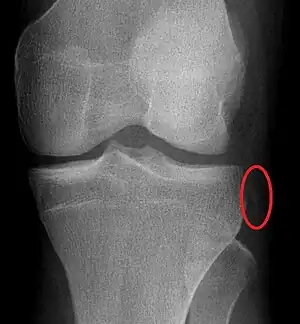

Plain X-rays, CT scan, ultrasonography, or MRI may help with the diagnosis.[2][11] Findings on X-ray that may be useful among those who have already reduced include a variable joint space, subluxation of the joint, or a Segond fracture.[5]

| Plain lateral X-ray of the left knee showing a posterior knee dislocation[1] | |